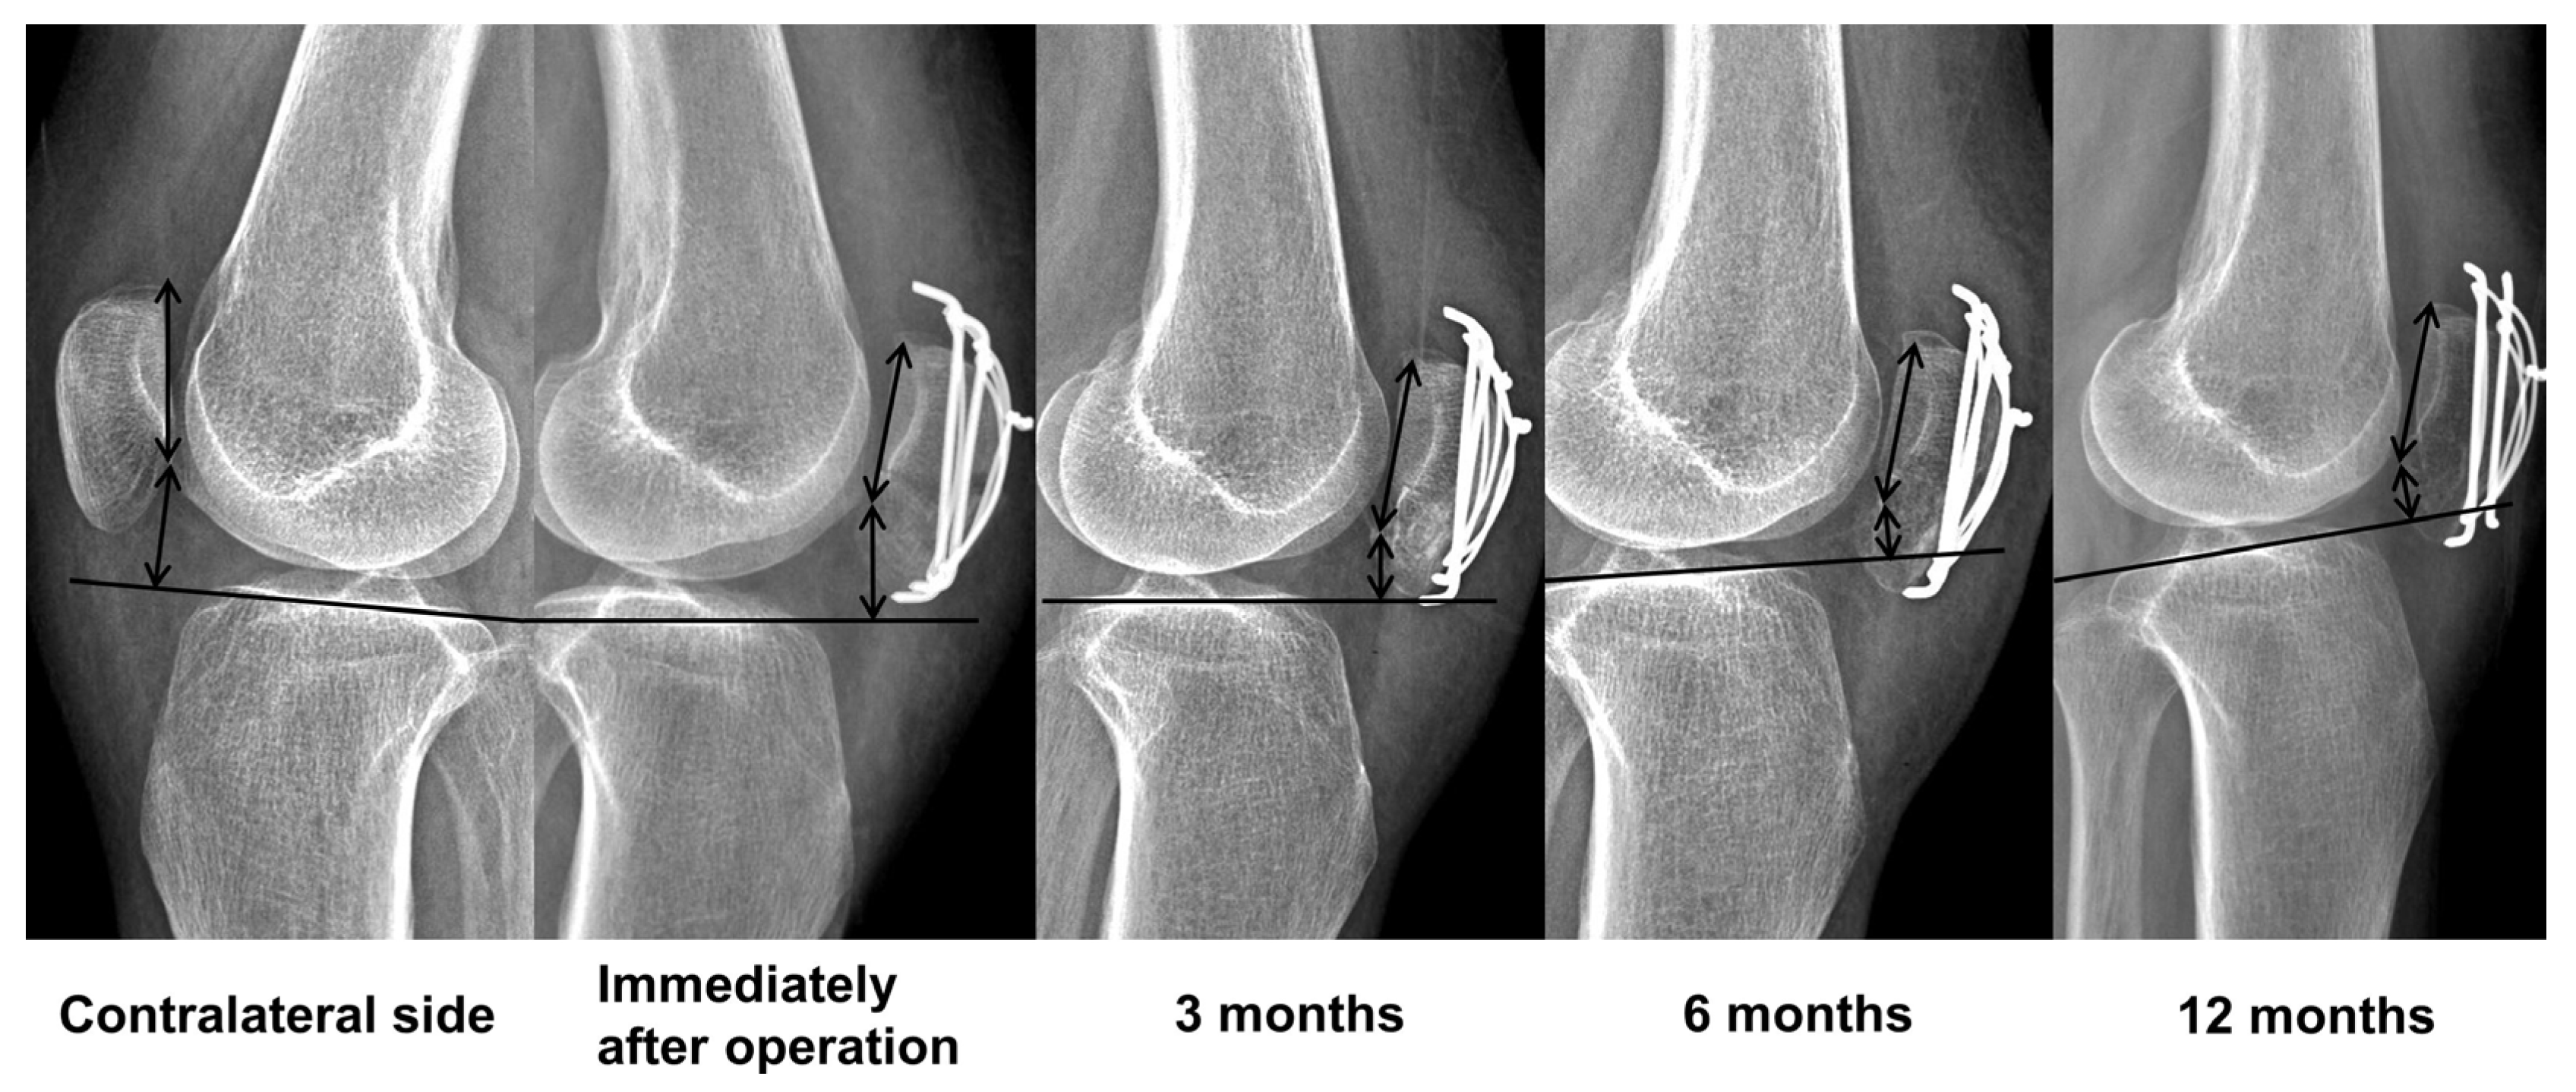

2.3. Clinical and Radiographic Assessments